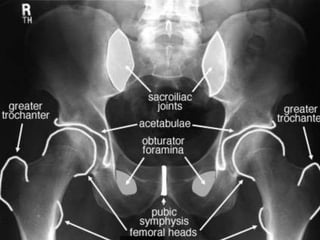

Radiographic Evaluation

• X-Ray AP view:

– Anterior lesions:

pubic rami fractures

– Symphysis

displacement

– Sacroiliac joint and

sacral fractures

– Iliac fractures

– L5 transverse

process fractures